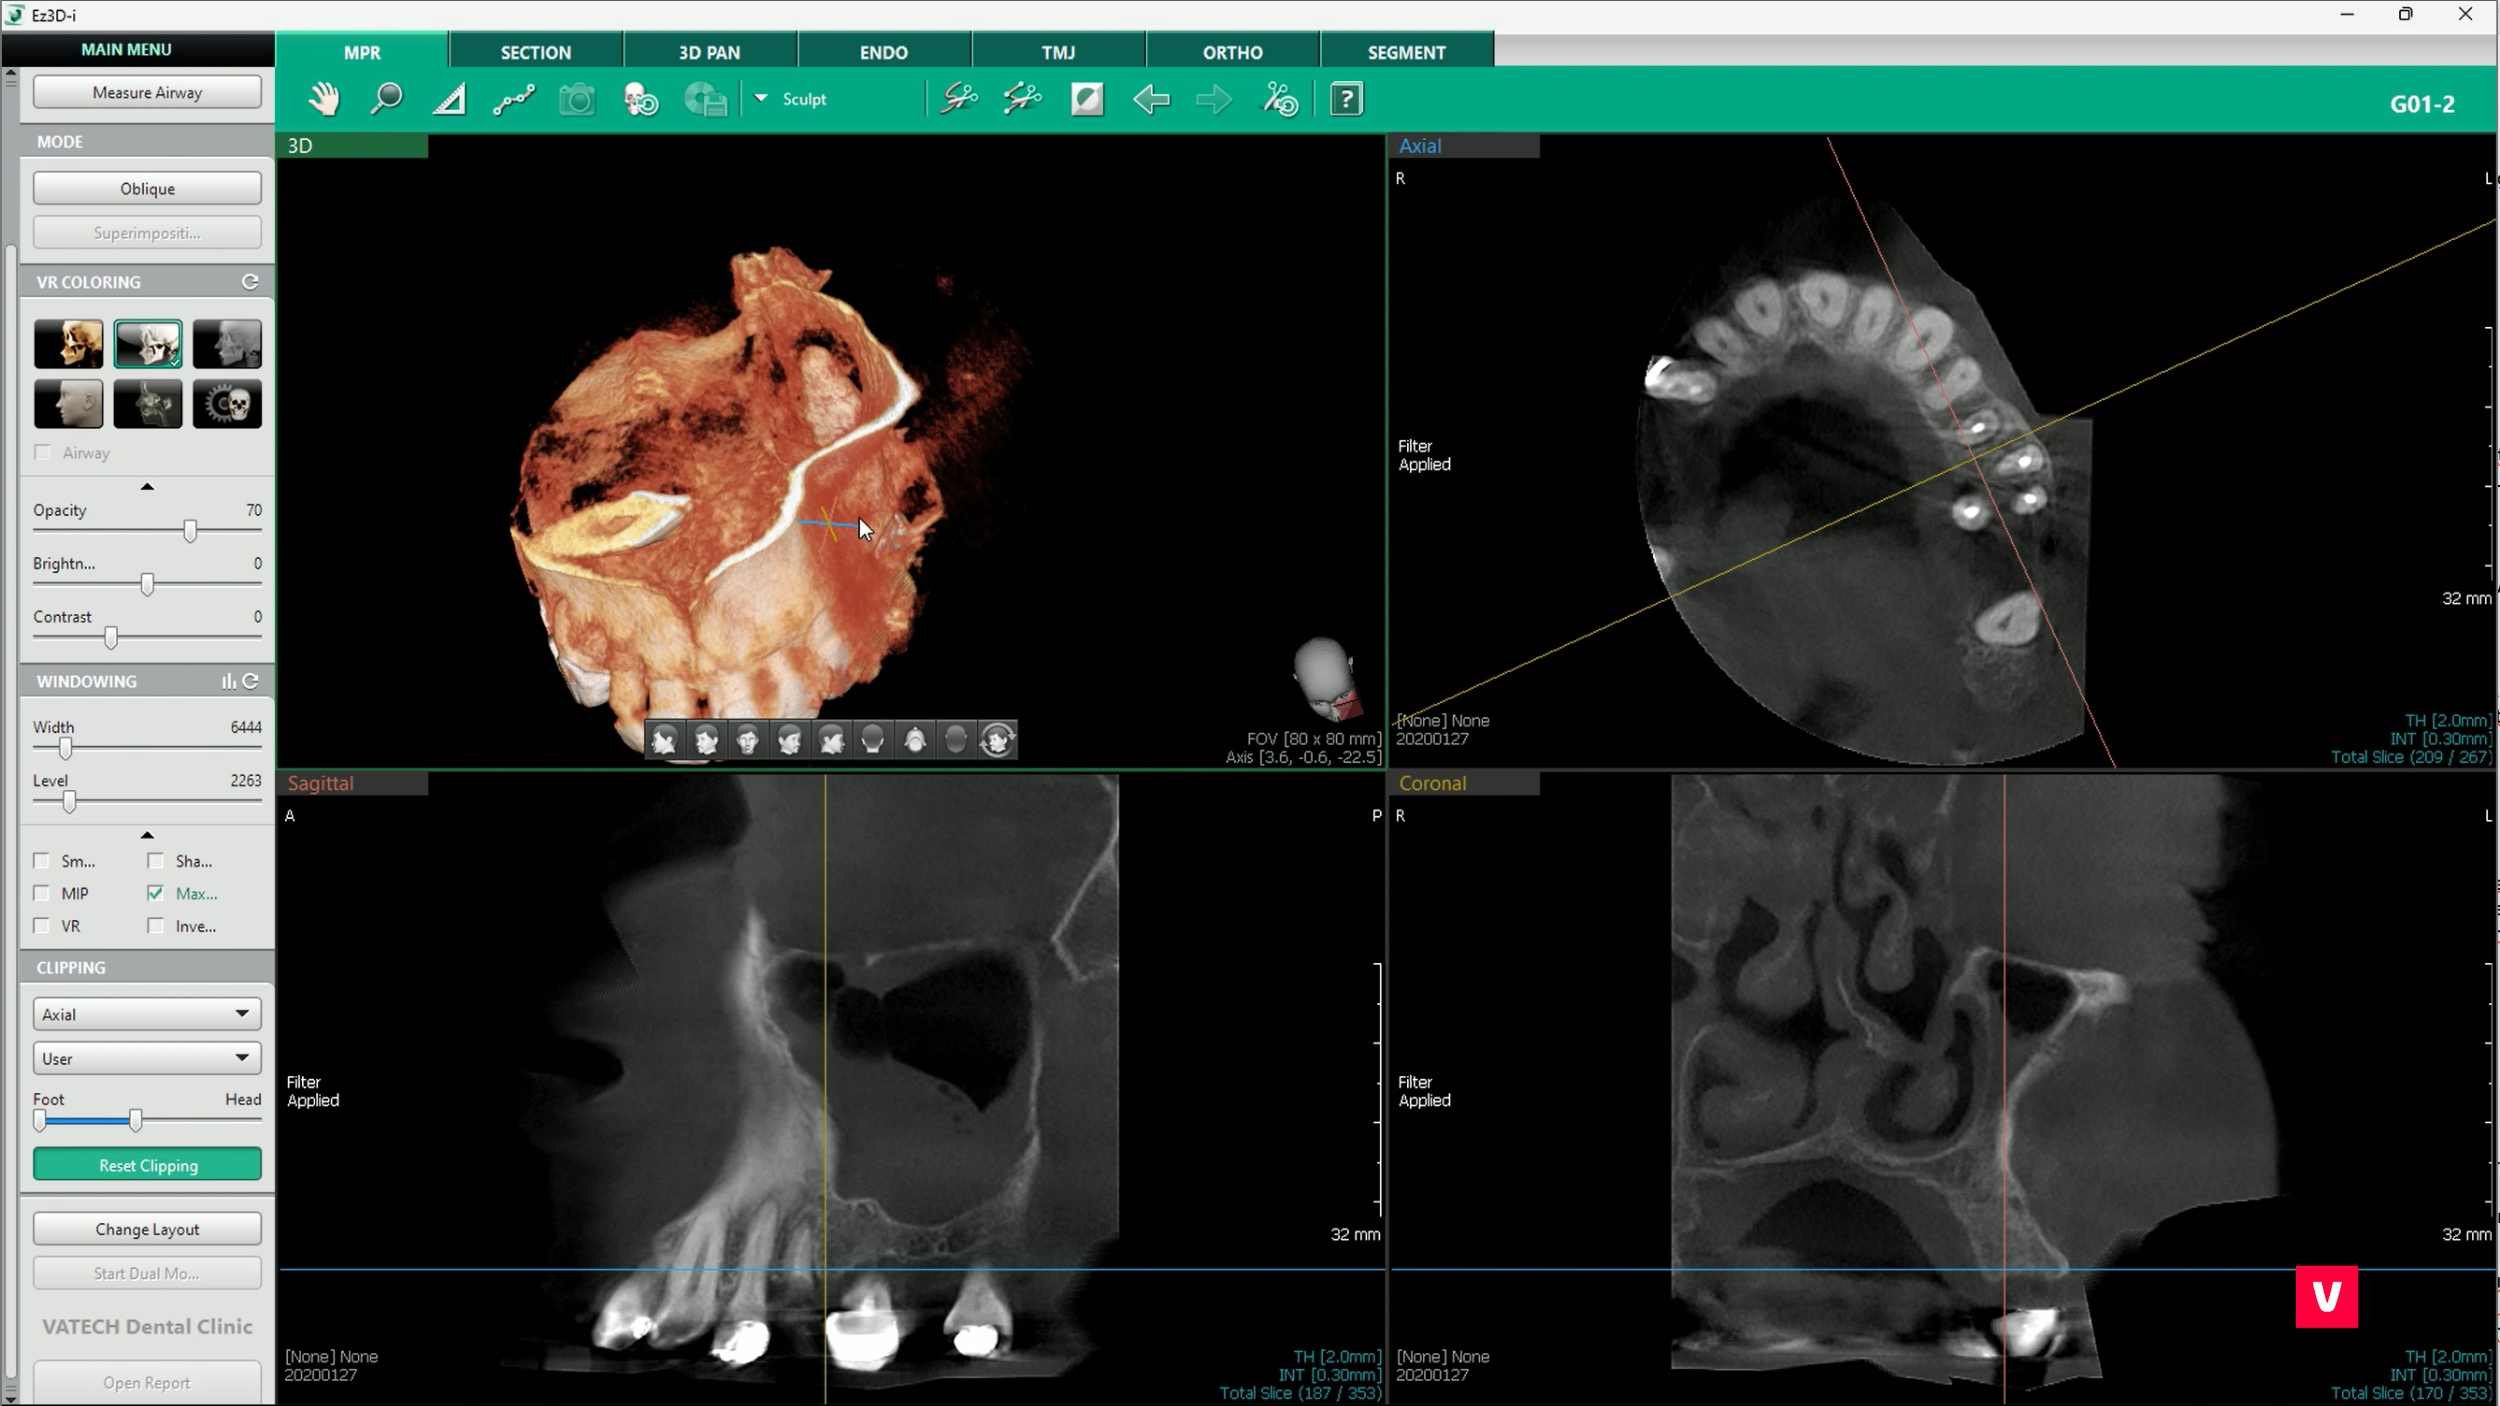

3. Măsurătorile

În abordarea diferitelor probleme de diagnostic, măsurătorile sunt extrem de utile pentru stomatologi. O măsurare adecvată poate face adesea diferența dintre o complicație nediagnosticată corect și un tratament de succes.

Din păcate, imaginile OPG nu oferă întotdeauna informațiile necesare pentru măsurarea corectă, iar distanța poate fi destul de distorsionată. Însă, distorsiunea nu este o îngrijorare pentru utilizatorii Ez3D-i, deoarece software-ul este echipat cu mai multe opțiuni de măsurare diferite, cum ar fi măsurarea lungimii, a lungimii multiple, a unghiurilor sau a razei unui cerc. Toate aceste funcții pot fi realizate cu ajutorul informațiilor adunate în timpul scanării 3D, astfel încât precizia lor este mult mai mare.

După cum se poate observa în acest studiu de caz prezentat, dintele ascuns în maxilar este mult mai aproape decât pare la o scanare OPG obișnuită. Acest lucru ar putea cauza unele probleme în timpul procedurilor stomatologice. Medicul stomatolog a identificat anomalia la timp, prevenind astfel complicațiile.